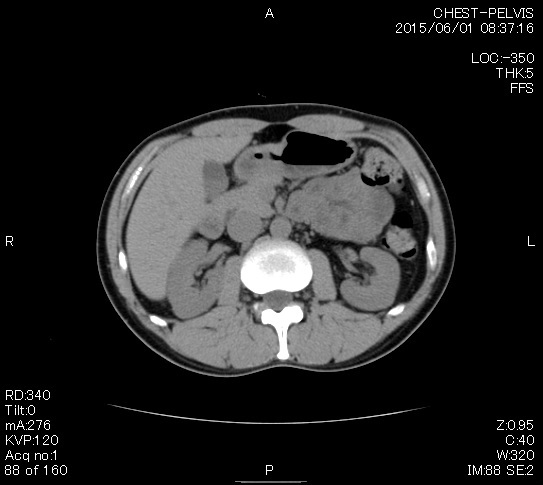

とうとうやってきた、この日が。

2006年入院治療の退院日から10年。 かなり大きな節目なんだが、なんだろうこの軽い感じは(笑)。 「10年生きたんだぁ」くらい。 変わったような変わっていないような。 当時は10年後なんて全く考えていなかった。 今も10年後は考えていないが・・・。 退院前日の2006/10/31は46.6kgだった。 今日計ったら54.8kg。体脂肪は16.6%。 とても健康にストレスなく生活できていることに、治療当時から現在に至るまで、関わった人全員に感謝の気持ちです。 マーカー、CT画像、問題なし!! 血液検査結果もほとんど文句なしの正常値。 そうだなぁ、数値に出ない異変としては、肩凝りかなぁ。 一旦夏になくなったと思ったが、初秋から再発。 マウスを左手にしたり、シップ貼ったり、最近はホッカイロ貼ったり。 で、一向に良くなる気配がない。 やはり四十肩なのか。 でも肩の可動域は問題ない。動かせないような痛みも無い。 結局色々考えてたどり着いたのは「変形性頚椎症」ではないかと。 肩凝りや頭痛がダラダラと続くようになるという症状がピッタリ当てはまる。 さて、改善策がなかなか難しい。 整形外科行ってもレントゲン撮って湿布をくれるだけだろう。 そんなことに大金を出すならまずは300円/回のプールで泳ごうと思う。 重力から開放して全身運動をするのが一番良いらしい。 2015年の目標は少しでも良いから水泳を再開する、だな。 マーカー、CT画像、問題なし!! 通常の血液検査結果も文句なしの正常値がズラ~っと並んだ!! 間違いなくヨメの食事のおかげである。ほんとうに感謝である!! ちなみに最近少々腰周りの肉付きが気になっていたのだが・・・。 左から2013年12月、2013年06月、2012年12月と背骨の位置は合わせて並べてみた。 6月まではあまり変化がなかったが、この半年で明らかに違う。 背中側の脂肪がやや増えてはいる。 でも最も大きな違いは、腸なのか、やたらと内臓が膨れている・・・。 一言で言うと食べすぎ?!?! 食事は野菜中心ではあるが、確かによく食べているw。 せっかくスーツのウエストを詰めたんだからこれ以上にならないようにしたい。 「腹八分目を心がける」かな。